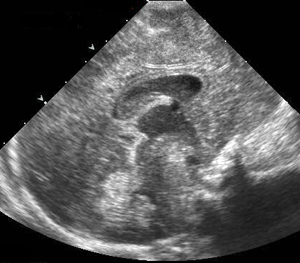

Pediatric cranial sonogram.

Pediatric Imaging

Dramatic advances in imaging technologies are improving the ability of pediatric radiologists to diagnose complex cases in children. For all imaging of children at UCSF we pay special attention to ensuring that protocols are pediatric specific and that all imaging studies are interpreted by radiologists who are specially trained in pediatric anatomy and pathology. UCSF ascribes to the policy of “imaging gently“[1] in the imaging of children, and the use of ultrasound is an important tool in achieving that goal.

UCSF’s ultrasound subspecialty has world-renowned experts in prenatal ultrasound imaging as well as for children and babies. Our expert staff includes specialists in prenatal imaging of congenital anomalies and fetal therapy.